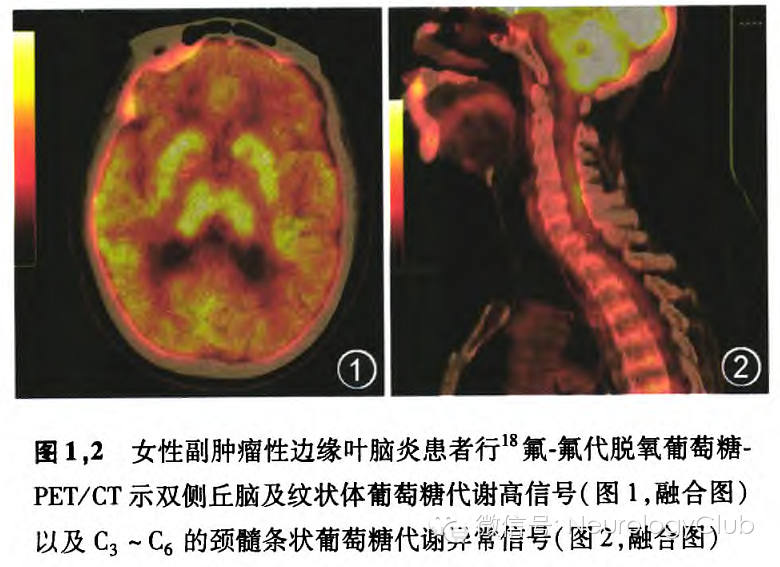

副肿瘤性LE常有边缘系统症状之外的体征,可表现为副肿瘤性脑脊髓炎。通常与小细胞肺癌相关。在副肿瘤综合征患者中有2/3在确诊肿瘤之前出现神经系统症状所有的LE患者都应进行肿瘤筛查,首选氟代脱氧葡萄糖(FDG)-PET/CT扫描。笔者曾遇到数例副肿瘤性LE患者,其中1例女性65岁患者因“进行性双下肢麻木乏力半年,反应迟钝伴精神症状1个月”入院,脑部表现完全符合LE。其全身FDG-PET/CT扫描可见大脑(图1)、颈髓(图2)均显示副肿瘤性脑脊髓炎的高代谢表现,并发现肺癌病灶。张祥等的研究还发现抗N-甲基-D-天冬氨酸(NMDA)受体脑炎患者在疾病不同时期的脑18F-FDG PET/CT显像表现为18F-FDG由增高到减低的过程,可能累及部位主要有额颞枕顶叶皮质、基底节及小脑,以左侧大脑半球及右侧小脑为主,在实践中应注意观察这些特点影像。此外,对副肿瘤性LE也需要行颈胸腹的CT检查,男性尤其应该注意睾丸检查副肿瘤性LE的确诊需要具备临床表现、边缘系统受累的形态学证据、抗体检测阳性及起病后5年内发现肿瘤等条件

此外,脑脊液中若淋巴细胞增多,蛋白升高,寡克隆区带阳性对支持诊断提供参考依据。MRI在T1WI和FLAIR像(此像位更加敏感)可见颞叶内侧高信号。往往脑电图可能会出现局灶性或广泛性慢波异常或癫痫样放电表现。有的即使MRI是正常的,但FDG-PET/CT也可检测到颞叶海马代谢亢进。